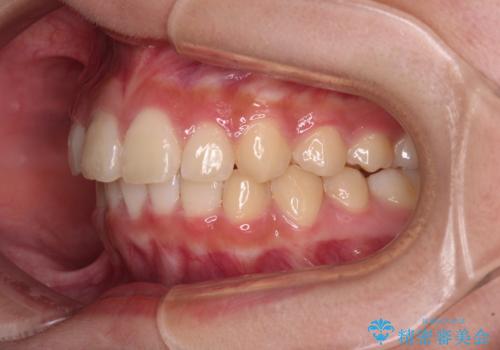

ワイヤー装置と補助装置を有効に活用し、さらには高校生ということもあり、1年9か月で狙い通りの仕上がりを達成することができました。